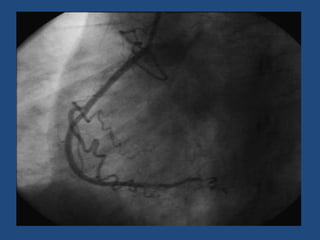

STENT

FALSA LUZ

SONDA

LUZ